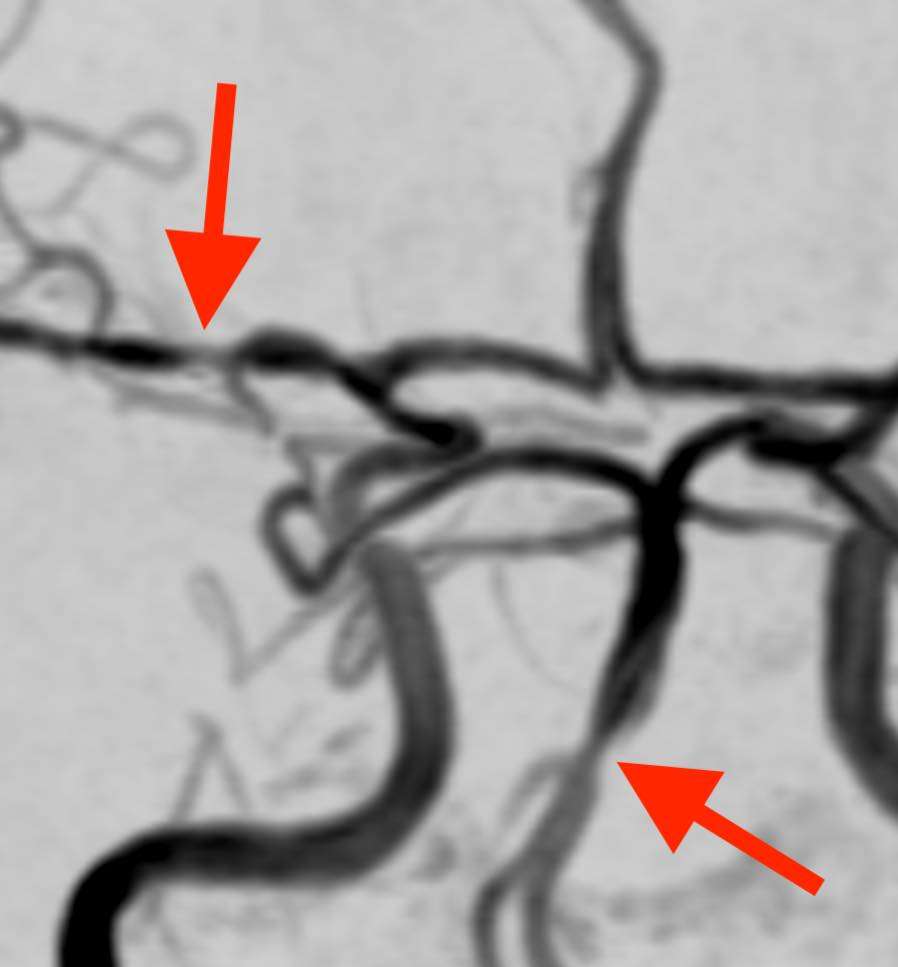

頭部MRA検査で脳の血管を撮影しました。

脳動脈にくびれた部分と膨らんだ部分とが見られ、脳血管の収縮と拡張を示します。

したがって、症状の経過と画像所見から、可逆性脳血管攣縮症候群(RCVS)と診断しました。